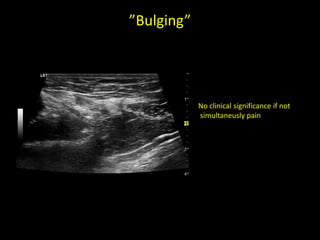

”Bulging”

No clinical significance if not

simultaneusly pain

”Bulging” No clinical significanceif not simultaneusly pain